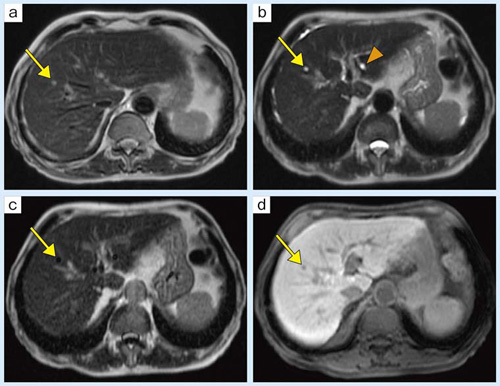

MixiMRI勉強会 脂肪抑制いろいろ 最近やっと勉強する気になったのですが、疑問が次から次へと出てきます。ここでは脂肪抑制についてお聞きしたいと思います。 脂肪抑制にもいろいろありますよね。 T2、PD、T1など。また、SE系、GRE系の違いもありま. ・骨盤部ではmriを,腹部ではctを第一選択にする. ・t1強調画像ではt1が長いほど磁化の回復が遅れるため信号が低く(黒く),t2強調画像ではt2 が長いほど磁化の減衰が遅れるため信号が高く(白く)描出される.t1とt2の組み合わせで組 t1強調画像はctの画像と似ており、脳の解剖学的な構造が見やすいという特徴があります。. 造影剤投与によりT1緩和時間が大きく短縮されますので基本的に脂肪抑制T1強調画像をベースに撮影が行われます。 ③実際の症例を提示します。 1) Stage I 腎細胞癌のdynamic MRI画像です。 左腎臓上極に1cm大の遷延性濃染する腫瘍を認めます。.

Nuclear Magnetic Resonance (Image). リウマチは関節内に存在する滑膜という組織が異常増殖し、関節内に慢性の炎症を生じる病気で、進行するとさまざまな機能障害を引き起こします 現在、当クリニックでは上腹部MRI検査として、横断像を4シーケンス<T1(in、 out Phase)T2 HeavyT2 DWI>、冠状断. T1強調像(Axial) T2強調像(Axial) 内膜症性嚢胞(チョコレート嚢胞) multiplicity.

腹部 Mri 検査 嚢胞性腫瘍は多様な像を呈し A T1 強調像では嚢胞は概ね低信号で一 部が高信号 B T2 Download Scientific Diagram

腹部 Mri 検査 嚢胞性腫瘍は多様な像を呈し A T1 強調像では嚢胞は概ね低信号で一 部が高信号 B T2 Download Scientific Diagram